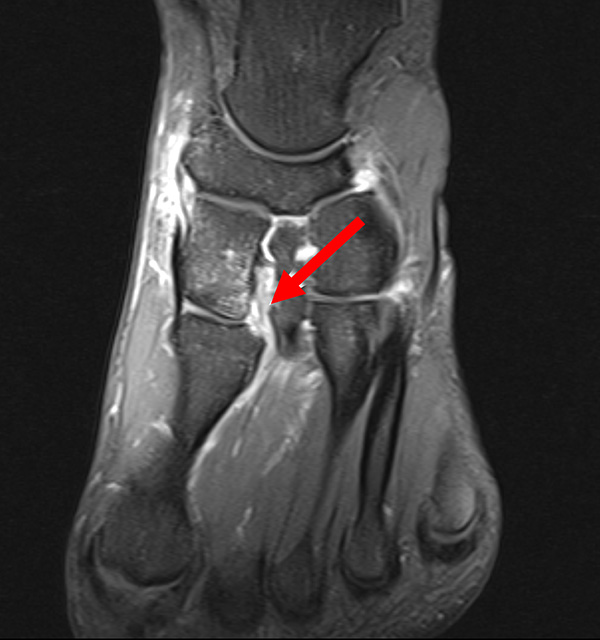

Das Lisfranc-Ligament selbst lässt sich am Besten im MRT beurteilen. Gelegentlich lässt sich im MRT ein Knochenmarksödem als einziges Zeichen einer nicht dislozierten Fraktur finden. Die MRT-Diagnostik ist allerdings eher unklaren interossären Erweiterungen bei persistierenden Schmerzen zur Suche nach isolierten Bandverletzungen vorbehalten 7511.

Zum Lesen der Bildbeschreibung und zur Vollansicht bitte das Bild anklicken.